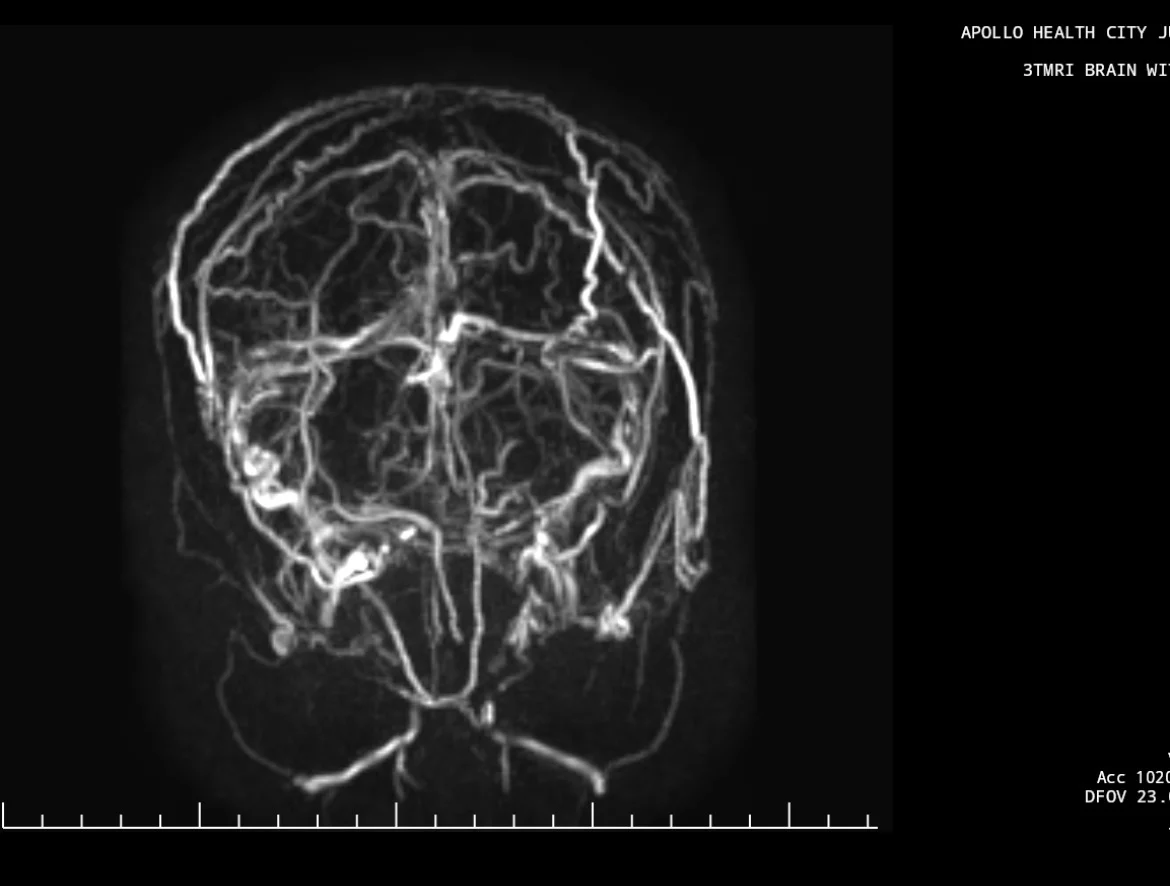

MRI FLAIR and MRI Venogram pictures are attached.

- MR Venogram shows Non-visualization of a major venous sinus, along with collateral venous channels

- MRI brain may be normal early; don’t miss this.